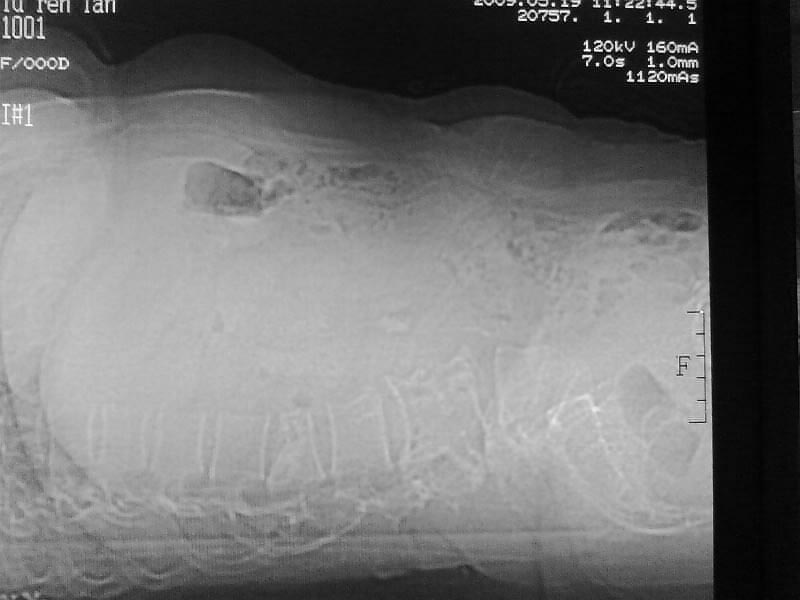

定位相示l2呈楔形改变(ct示陈旧性骨折改变,图像未传),l4.5椎体融合,以下是l4.5ct平扫.请各位看看,

定位像咋看也是腰一压缩性骨折,因为它上面的一个椎体的肋骨。

1、l1压缩性骨折(陈旧性)。

就是腰1压缩性骨折,腰3\\4椎体结核(融合),水平骶椎.

是l1压缩,不是l2写错了

支持 l1椎体陈旧性压缩性骨折;l3、4椎体结核(融合);水平骶椎。